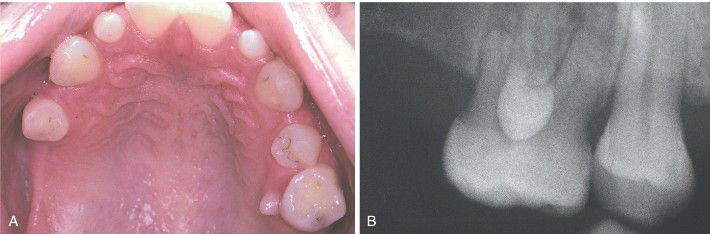

Paramolar

Rudimentary tooth situated palatal to a maxillary molar in a patient who also exhibits hypodontia. B, Radiograph of the same patient showing a fully formed tooth overlying the crown of the adjacent molar.